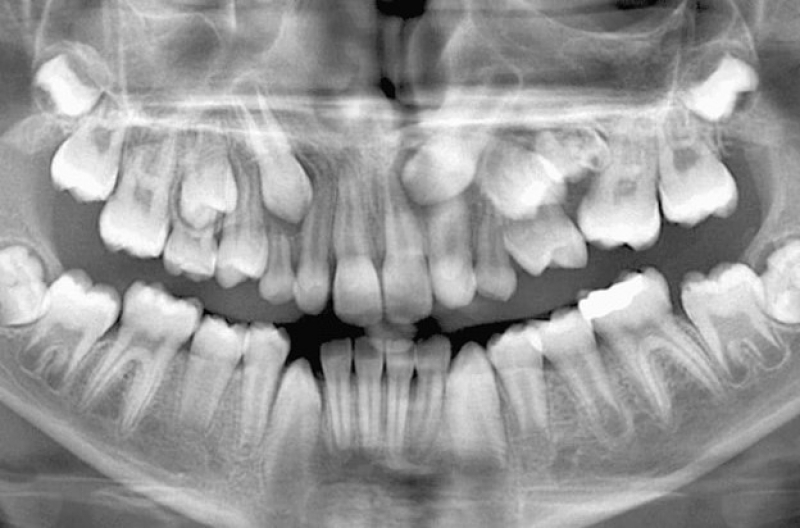

Главный метод исследования – рентгенография, КТ, которые позволяют изучать лишний зуб/ы. Главными критериями оценки будут:

· коронка зуба: ее форма, степень развития, отдельно стоящая или спаянная с другим зачатком зуба;

· корень. Напомним: молочные и постоянные зубы прорезываются в полости рта без корней, но на снимках можно заметить зону роста, что указывает на то, что зуб сможет стать полноценным и в полной мере выполнять все свои функции. На нём стоматолог может понять, какой зуб является комплектным, а какой лишним;

· степень развития сверхкомплектного зуба;

· правильность положения зачатка в челюсти.

Для решения судьбы сверхкомплектных зубов необходимо длительное и тщательное обследование ребенка: рентгенография (прицельный снимок), ортопантомомграмма (панорамный снимок – для оценки состояния зачатков и их соотношения), стоматологические тесты, консультации нескольких врачей стоматологической специальности.